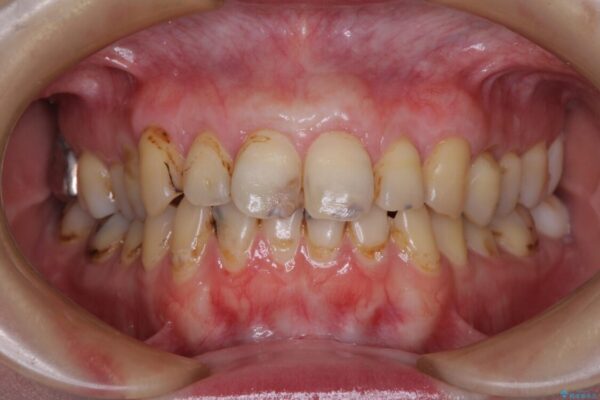

上下前歯や奥歯の虫歯治療を希望して来院された患者様です。

全顎的にむし歯が多く、根管治療の必要な奥歯や、審美的に気になっている前歯を中心にオールセラミッククラウンにて補綴治療を行うこととしました。

上顎前歯は歯肉退縮により歯根が露出していたため、事前に歯肉移植術により根面被覆を行い、その後にオールセラミッククラウンを装着することとしました。

治療前

• むし歯だらけの前歯をオールセラミッククラウンできれいに 治療前画像